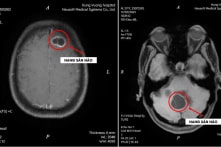

Thường xuyên ăn tiết canh, sán làm tổ trong não

Không sốt, yếu liệt hay khó thở, song hình ảnh chụp CT cho thấy trong não bệnh nhân, sán dây chó đã kết thành nang lớn. Bệnh viện đa khoa Hùng Vương ngày 30/11 cho…